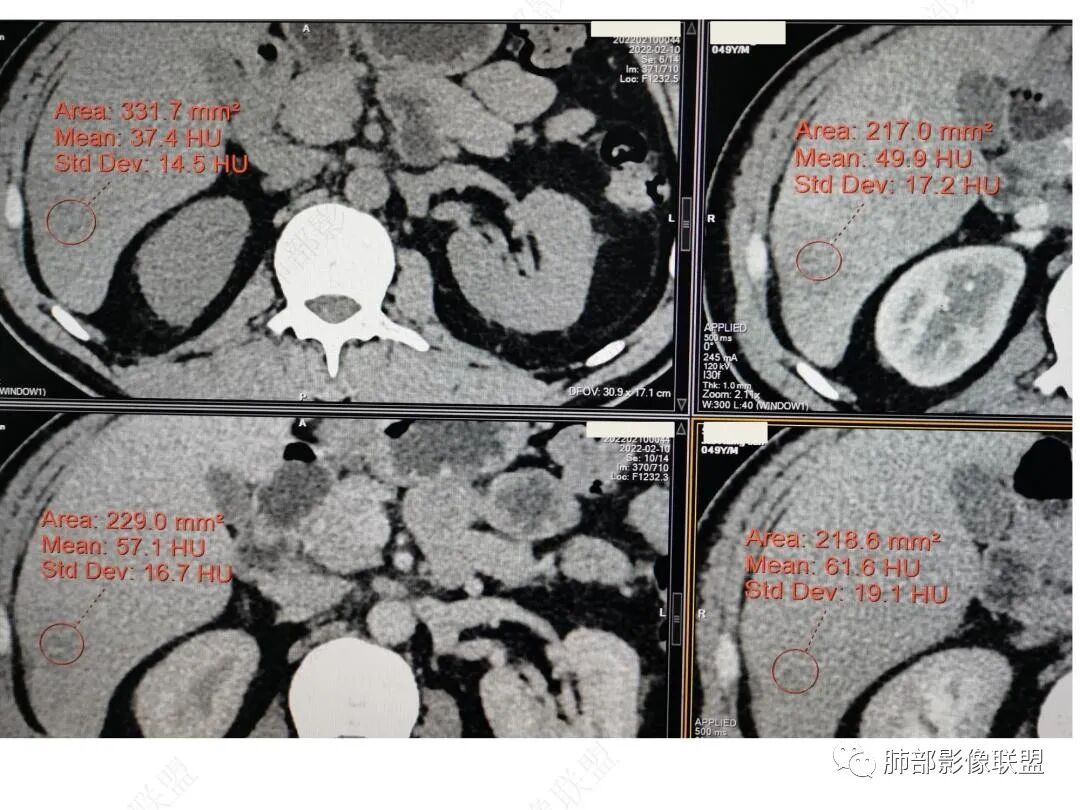

CT值信息

肝脏病变明确,是轻度强化,延迟强化特点,边缘模糊,有轻微的包膜挛缩。

4.肝脏病灶没有假包膜,没有动脉早期强化,没有肝硬化,未见扩张胆管,未见环形强化,也未显示靶征,缺乏肝细胞肝癌、胆管细胞癌、转移癌或肝脓肿特征。

但回顾性分析,如此少血供确实可以符合淋巴瘤,如果密度更均匀一点的话,这是我们有所忽略的地方。